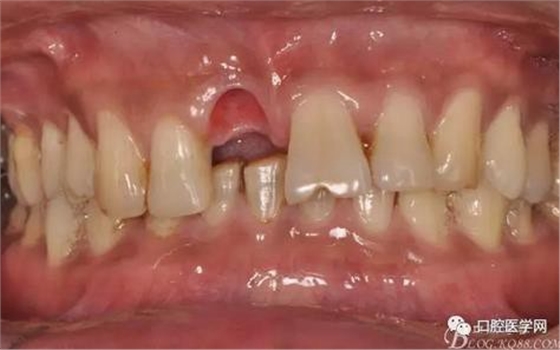

圖9 三個(gè)月后袖口形成正位照

圖10 三個(gè)月后袖口形成頜面照